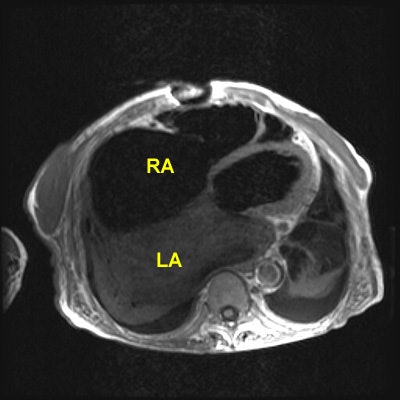

Rheumatic Fever

The patient shown below had a long history of valvular heart disease secondary to rheumatic fever. Both mitral and tricuspid valves were involved. There is massive right atrial (RA) dilatation. The left atrium is also massively dilated. Increased signal within the left atrium is related to slow flow.